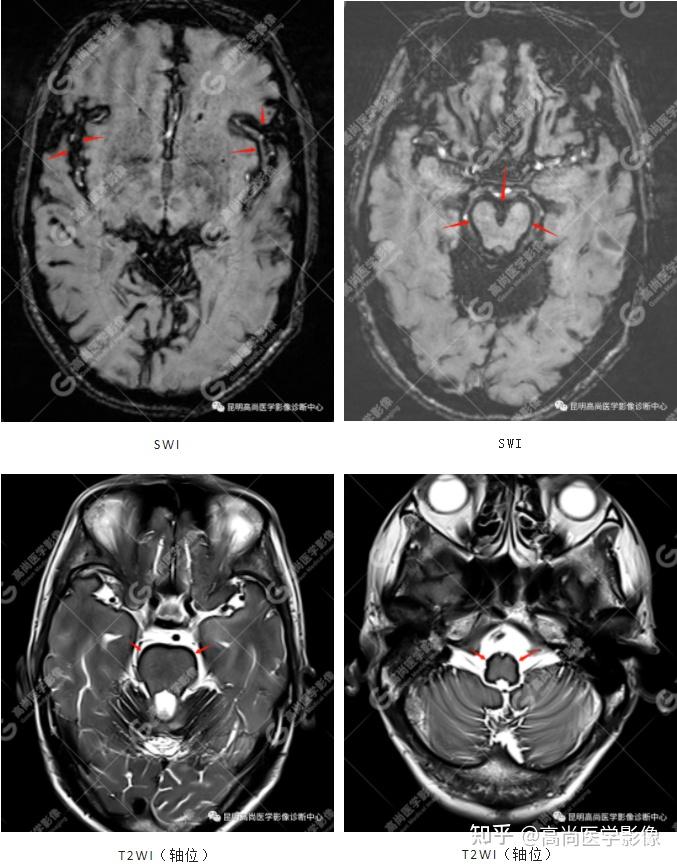

脑组织铁沉积神经变性病临床与影像诊断(二)

言语困难,表述不清,确诊:中枢神经系统表面铁质沉积症,伴轻度小脑萎缩